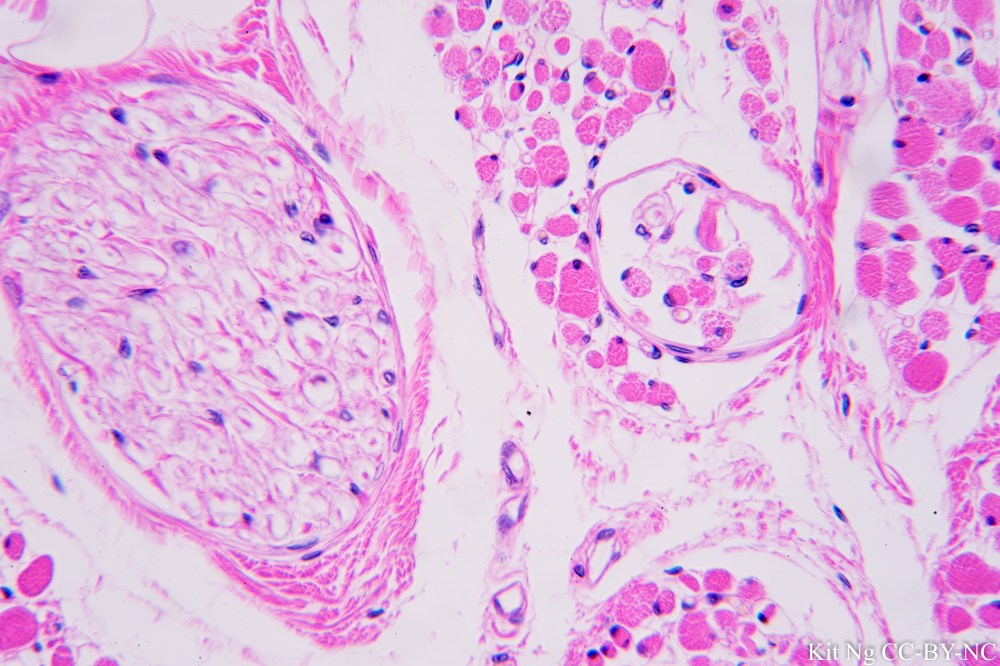

Below is a picture of a muscle in transverse section showing the difference between a peripheral nerve (left) and the muscle spindle (right). The spindle capsule, intrafusal muscle fiber and nerve fiber of gamma motorneurons with the nucleus of Schwann cell could be seen.